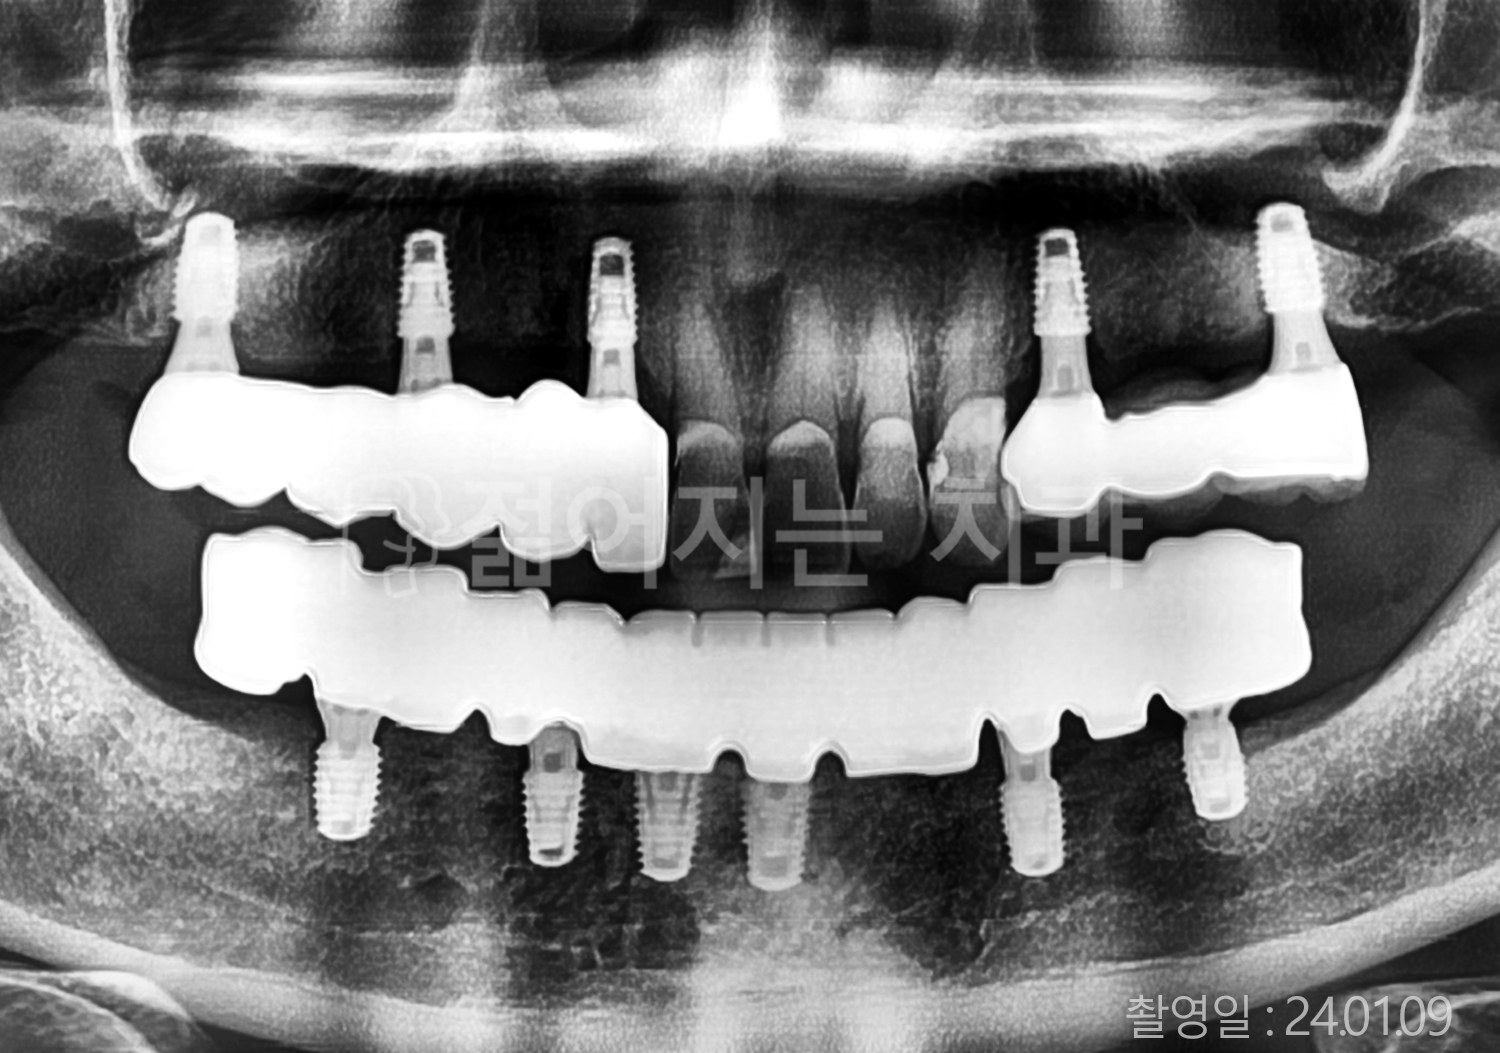

• 70대 고혈압, 고지혈증 전체치아 10개 이상 임플란트

• 60대 당뇨, 간염 전체치아 10개 이상 임플란트

• 80대 골다골증 전체치아 6개 이상 임플란트

• 70대 고혈압, 당뇨 전체치아 10개 이상 임플란트

• 60대 간 질환 전체치아 10개 이상 임플란트

• 60대 전체치아 10개 이상 임플란트

• 70대 전체치아 10개 이상 임플란트

• 50대 전체치아 10개 이상 임플란트

• 60대 고혈압, 고지혈증 전체치아 10개 이상 임플란트

• 40대 고지혈증, 뇌혈관 질환 전체치아 10개 이상 임플란트